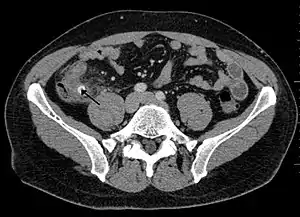

In children the clinical examination is important to determine which children with abdominal pain should receive immediate surgical consultation and which should receive diagnostic imaging.[42] Because of the health risks of exposing children to radiation, ultrasound is the preferred first choice with CT scan being a legitimate follow-up if the ultrasound is inconclusive.[43][44][45] CT scan is more accurate than ultrasound for the diagnosis of appendicitis in adults and adolescents. CT scan has a sensitivity of 94%, specificity of 95%. Ultrasonography had an overall sensitivity of 86%, a specificity of 81%.[46]

Computed tomography

Where it is readily available, computed tomography (CT) has become frequently used, especially in people whose diagnosis is not obvious on history and physical examination. Although some concerns about interpretation are identified, a 2019 Cochrane review found that sensitivity and specificity of CT for the diagnosis of acute appendicitis in adults was high.[51] Concerns about radiation tend to limit use of CT in pregnant women and children, especially with the increasingly widespread usage of MRI.[52][53]

The accurate diagnosis of appendicitis is multi-tiered, with the size of the appendix having the strongest positive predictive value, while indirect features can either increase or decrease sensitivity and specificity. A size of over 6 mm is both 95% sensitive and specific for appendicitis.[54]

However, because the appendix can be filled with fecal material, causing intraluminal distention, this criterion has shown limited utility in more recent meta-analyses.[55] This is as opposed to ultrasound, in which the wall of the appendix can be more easily distinguished from intraluminal feces. In such scenarios, ancillary features such as increased wall enhancement as compared to adjacent bowel and inflammation of the surrounding fat, or fat stranding, can be supportive of the diagnosis. However, their absence does not preclude it. In severe cases with perforation, an adjacent phlegmon or abscess can be seen. Dense fluid layering in the pelvis can also result, related to either pus or enteric spillage. When patients are thin or younger, the relative absence of fat can make the appendix and surrounding fat stranding difficult to see.[55]